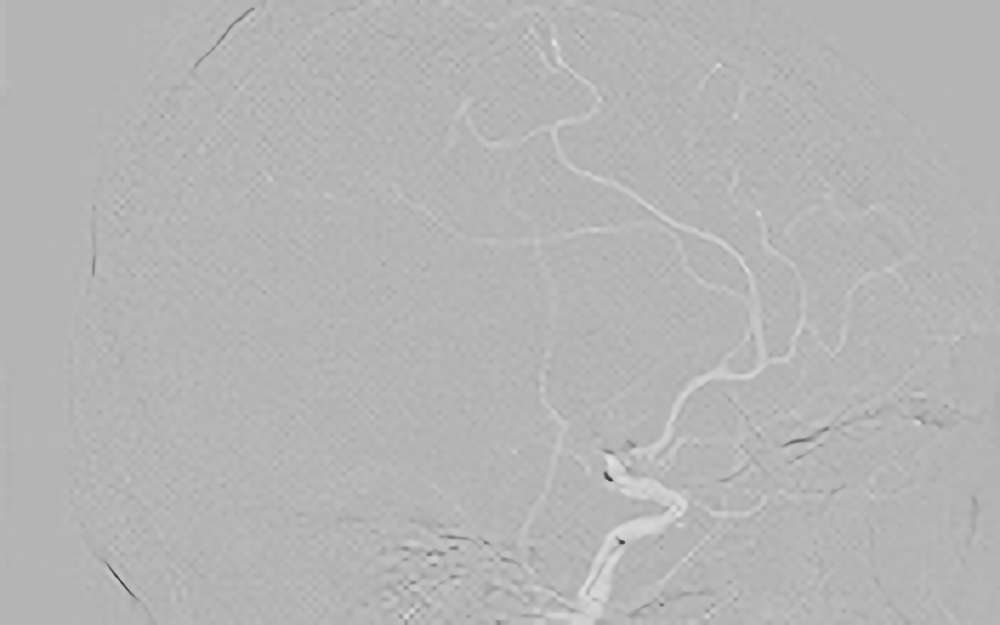

938

'20年11月7日

心原性脳塞栓症

80代

院内外来

手術写真

治療

前

中

後

手術日